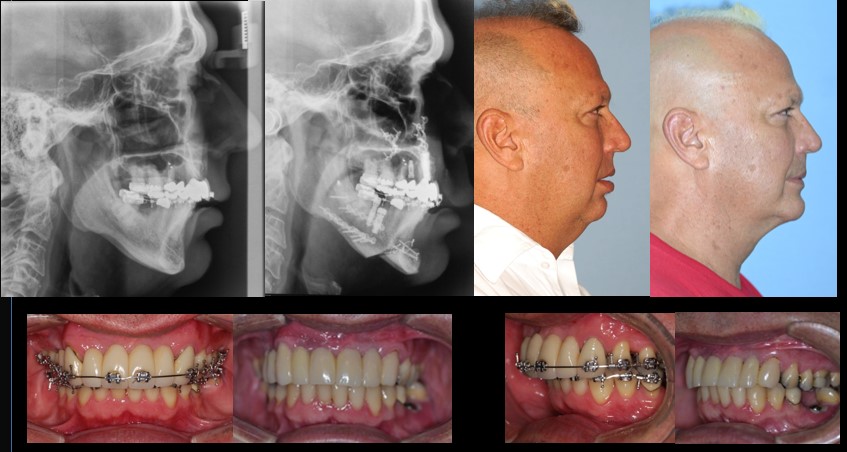

For over 30 years, Dr. Guerrero has made it his mission to improve the lives of his patients through specialized surgical care that restores function and comfort. Dr. Guerrero’s work embodies precision, compassion, and a dedication to patient well-being. Corrective jaw surgery is one of the advanced services offered, designed to address functional issues and enhance the quality of life for those who need realignment and reconstruction.